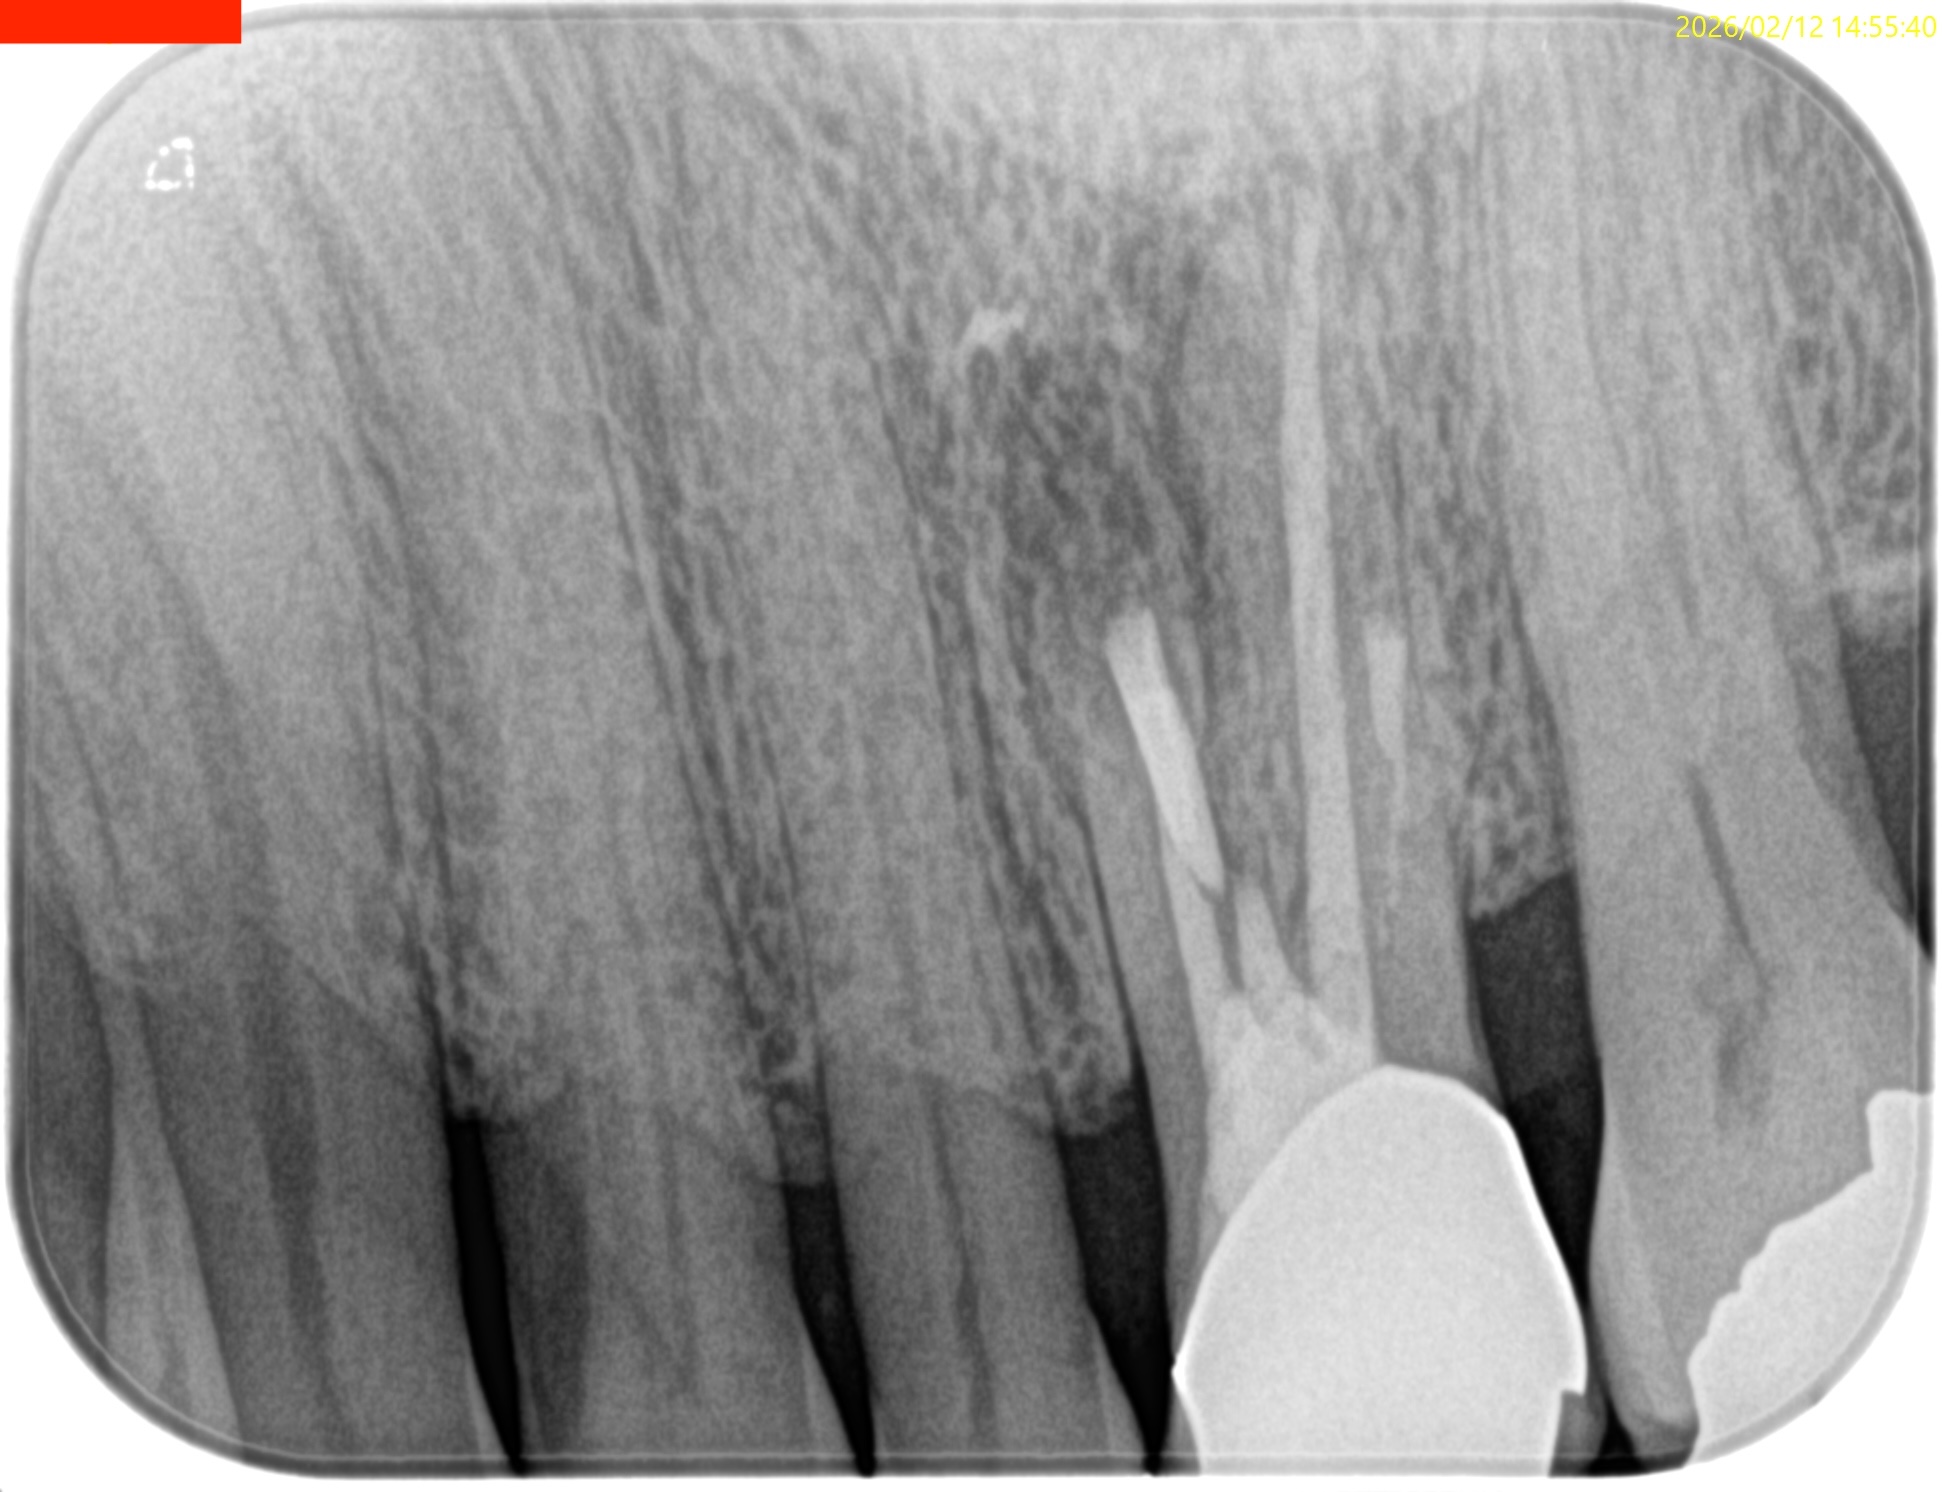

#14 MB,DB Apicoectomy(2026.2.12)

逆根充後にPA, CBCTを撮影した。

MB

DB

P

B